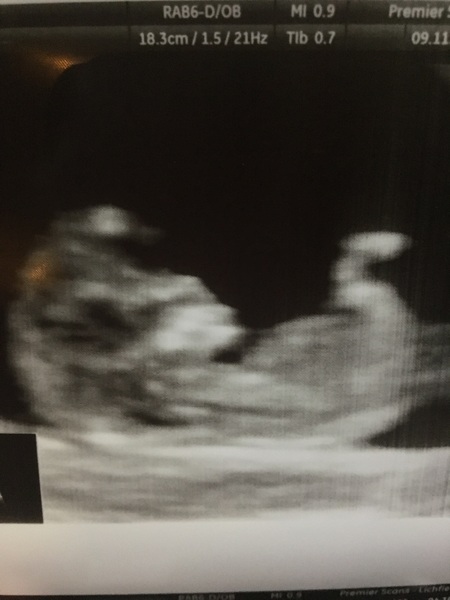

Tea I'm sure that is what it is - I have the same which is what worried me into getting yet another scan - just left there and everything was perfect and baby was having a right dance around!!

The sonographer told me that there is loads of twinges and bits of pain and it's normally just the stretching / growing / moving around xxx

Pic of baby ... I don't know how I'm gonna cope not having scans all the time after the 12 weeks! I'm on first name terms with my scan clinic!!

Thank you for reassurance mrspage and what a lovely scan pic! Baby is growing fast!